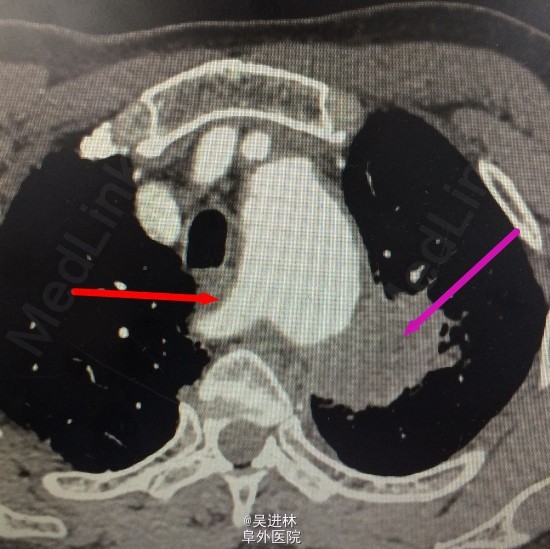

患者男,68岁,主因“左侧背部疼痛1月”以“肺占位”收入院。患者1月前无明显诱因出现左侧背部疼痛,无咳嗽咳痰,发热、咳血、喘憋、无力,于当地医院就诊,2015年05月18日查胸部CT示左肺上叶占位,大小约4*4cm,可见毛刺,未治疗。

辅助检查: 当地医院胸部CT示左肺上叶占位,大小约4*4cm,可见毛刺

讨论:我在图片中用两种颜色标记了两种东东,左边的是肺癌,但是,右边从主动脉弓上面分出一只血管(正常主动脉弓在这个水平没有分支),你知道这是什么血管吗?这种情况其实不少见哦,欢迎讨论!胸外科尤其做食管癌的时候,如果遇到这根血管,需谨慎,心中有数。